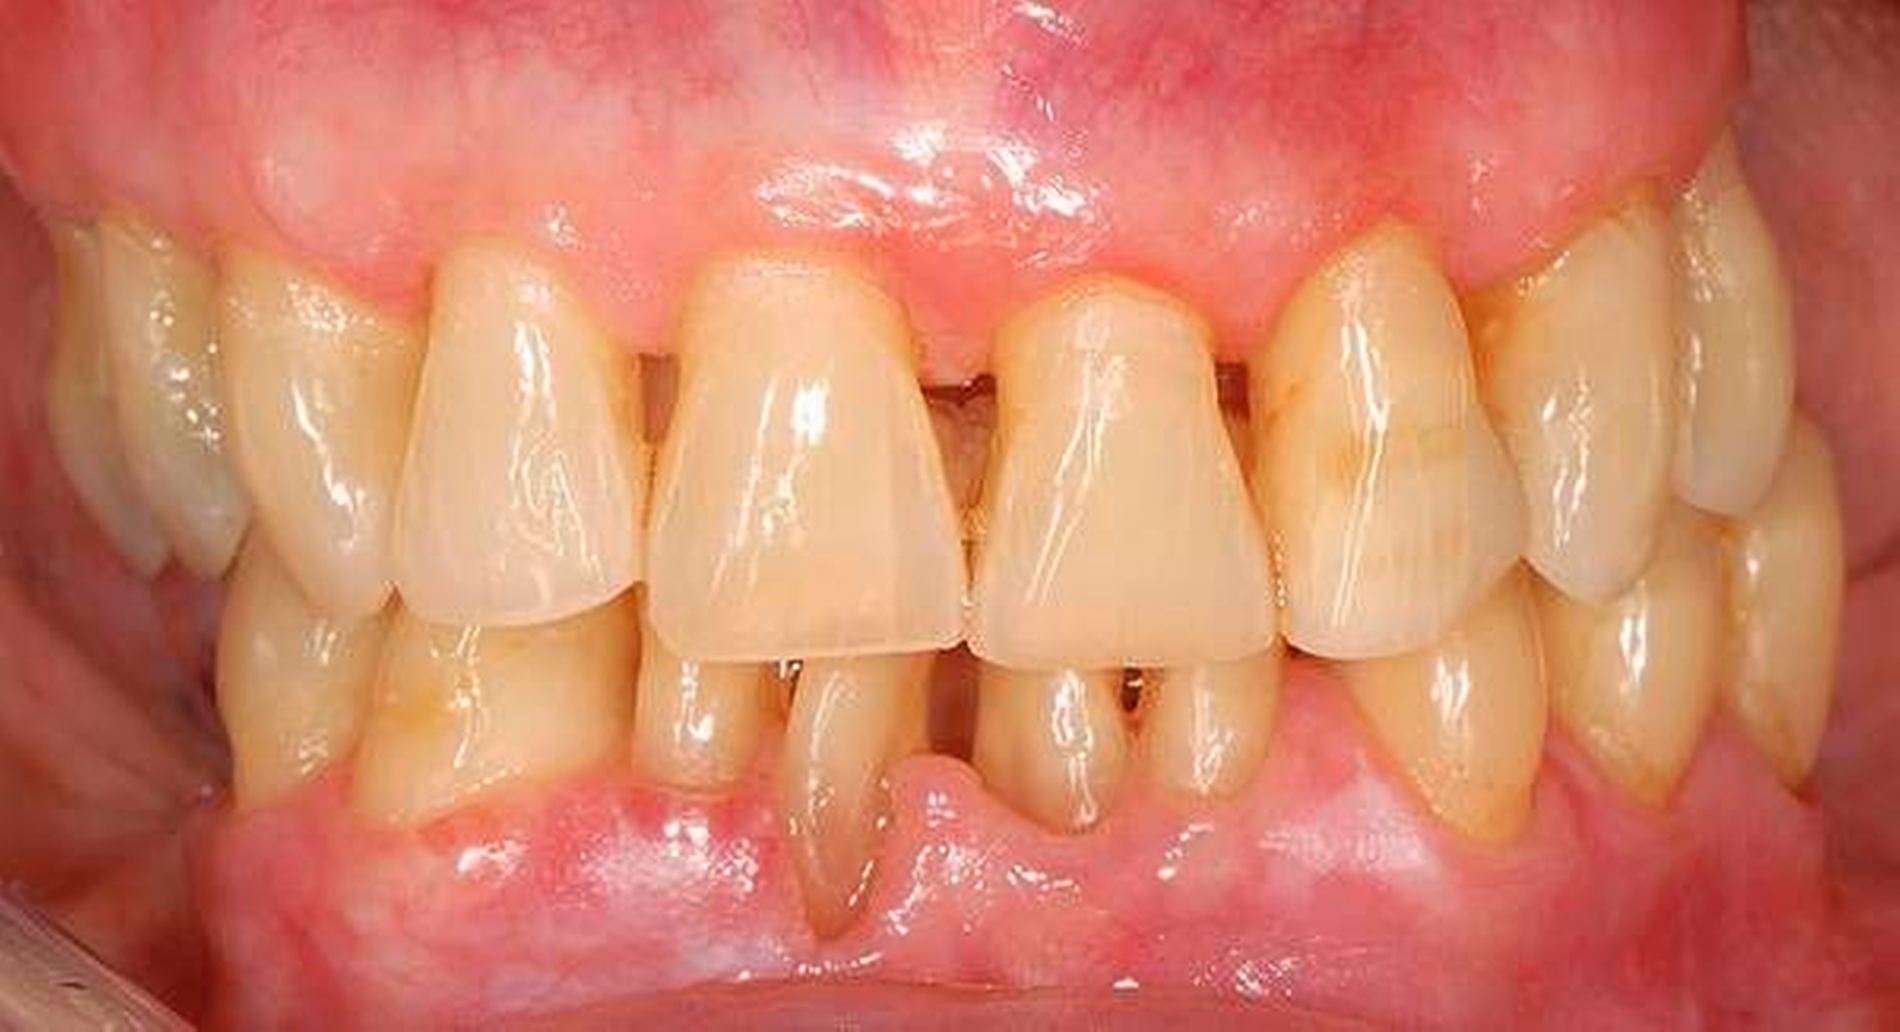

Abbildung 2: Direkte Teilüberkronung im Seitenzahnbereich (R1-Technik)

In den Abbildungen 1 bis 3 werden Optionen für frugale Interventionen auf restaurativem Sektor aufgeführt. Es handelt sich um direkte Vollüberkronungen im Frontzahnbereich (hier: hergestellt in R1-Technik / einphasig) (Abbildung 1), direkte Teilüberkronungen im Seitenzahnbereich (hier: hergestellt in R1-Technik / einphasig) (Abbildung 2), Reparatur-Restaurationen im Seitenzahnbereich (hier: hergestellt in R2-Technik / zweiphasig) (Abbildung 3). Technische Einzelheiten zur Vorgehensweise und den Ergebnissen sind an anderer Stelle beschrieben (Literatur siehe oben).

Für die in Abbildung 2 dargestellte Situation eines tief zerstörten Prämolaren gelten ähnliche Charakteristika. Es gibt in der restaurativen Zahnheilkunde viele Neuerungen, die das Behandlungsspektrum vergrößert haben. Dazu zählen unter anderem:

ein- oder zweiphasiges Vorgehen je nach Defektausdehnungen (R1- und R2-Technik),

von Präparationsgrenzen unabhängige Verschalungstechniken, die auch bei nicht-kariesbedingten Zahnhartsubstanzschäden (wie etwa Hypomineralisationen) zum Einsatz kommen können,

schadensgerechte Reparaturtechniken (Abbildung 3),

neuartige Insertionstechniken, die unter anderem die Anpassung neuer Restaurationen an vorhandene prothetische Versorgungen (Reziproktechnik) erlauben.